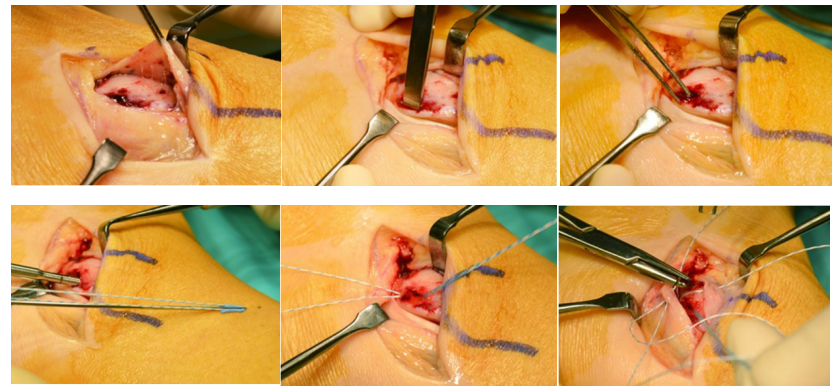

如不合并其他病理改变,可将支持带和骨膜直接缝合于外踝骨质上。

SPR撕脱开放手术锚钉修复